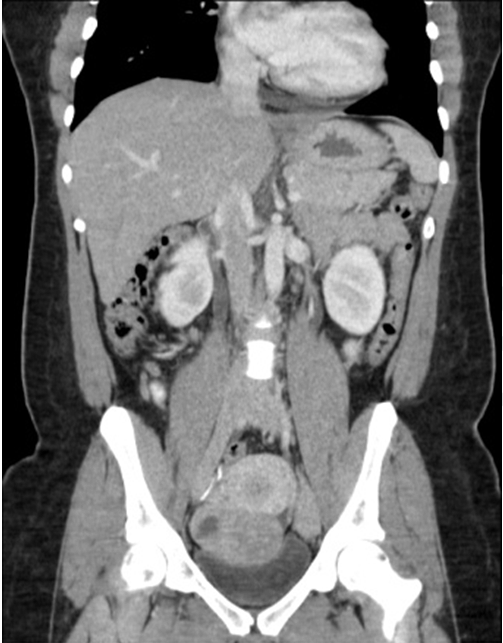

Patient followed with endocrine for continuous hirsutism and clitoromegally. Medical treatment of hirsutism was attempted with minimal response. In 2014, CT scan showed 7 cm adnexal mass with possible recurrence. Patient subsequently got pregnant (Figure 2) and (Figure 3). Testosterone and inhibin levels were still within normal limits. MRI scan showed 8x8x7 cm pelvic mass with cystic changes separate from the uterus (Figure 4) and (Figure 5). Case was discussed in tumor board with the presence of gynecological oncology, medical oncology, surgical oncology, radiology and MFM team. Anonymous decision was made to offer the patient surgery for suspected recurrent granulosa cell tumor of the ovary.

Figure 2: A 30-year-old female with suspected recurrent ovarian granulosa cell tumor in pregnancy. Contrast-enhanced coronal CT image showing heterogenous enhancing pelvic mass measuring 7.3x5x5.4 cm.